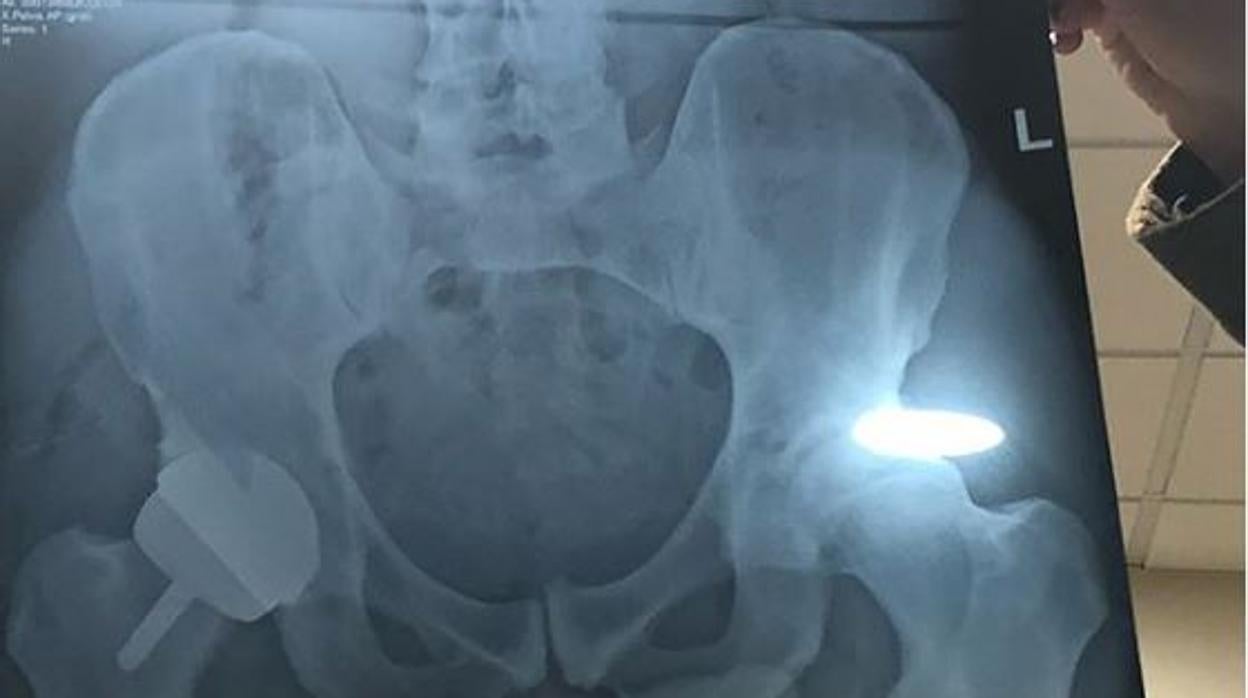

«Con suerte, este será el final de mi dolor en la cadera. Ahora tengo una cadera de metal» , compartió en su cuenta de Instagram junto a dos fotos, una tendido en la camilla, y otra de una radiografía. De lo que no se dio cuenta el escocés es de que en la imagen, además de sus huesos y la prótesis metálica que le habían colocado, también se podía ver con cierta nitidez su pene .